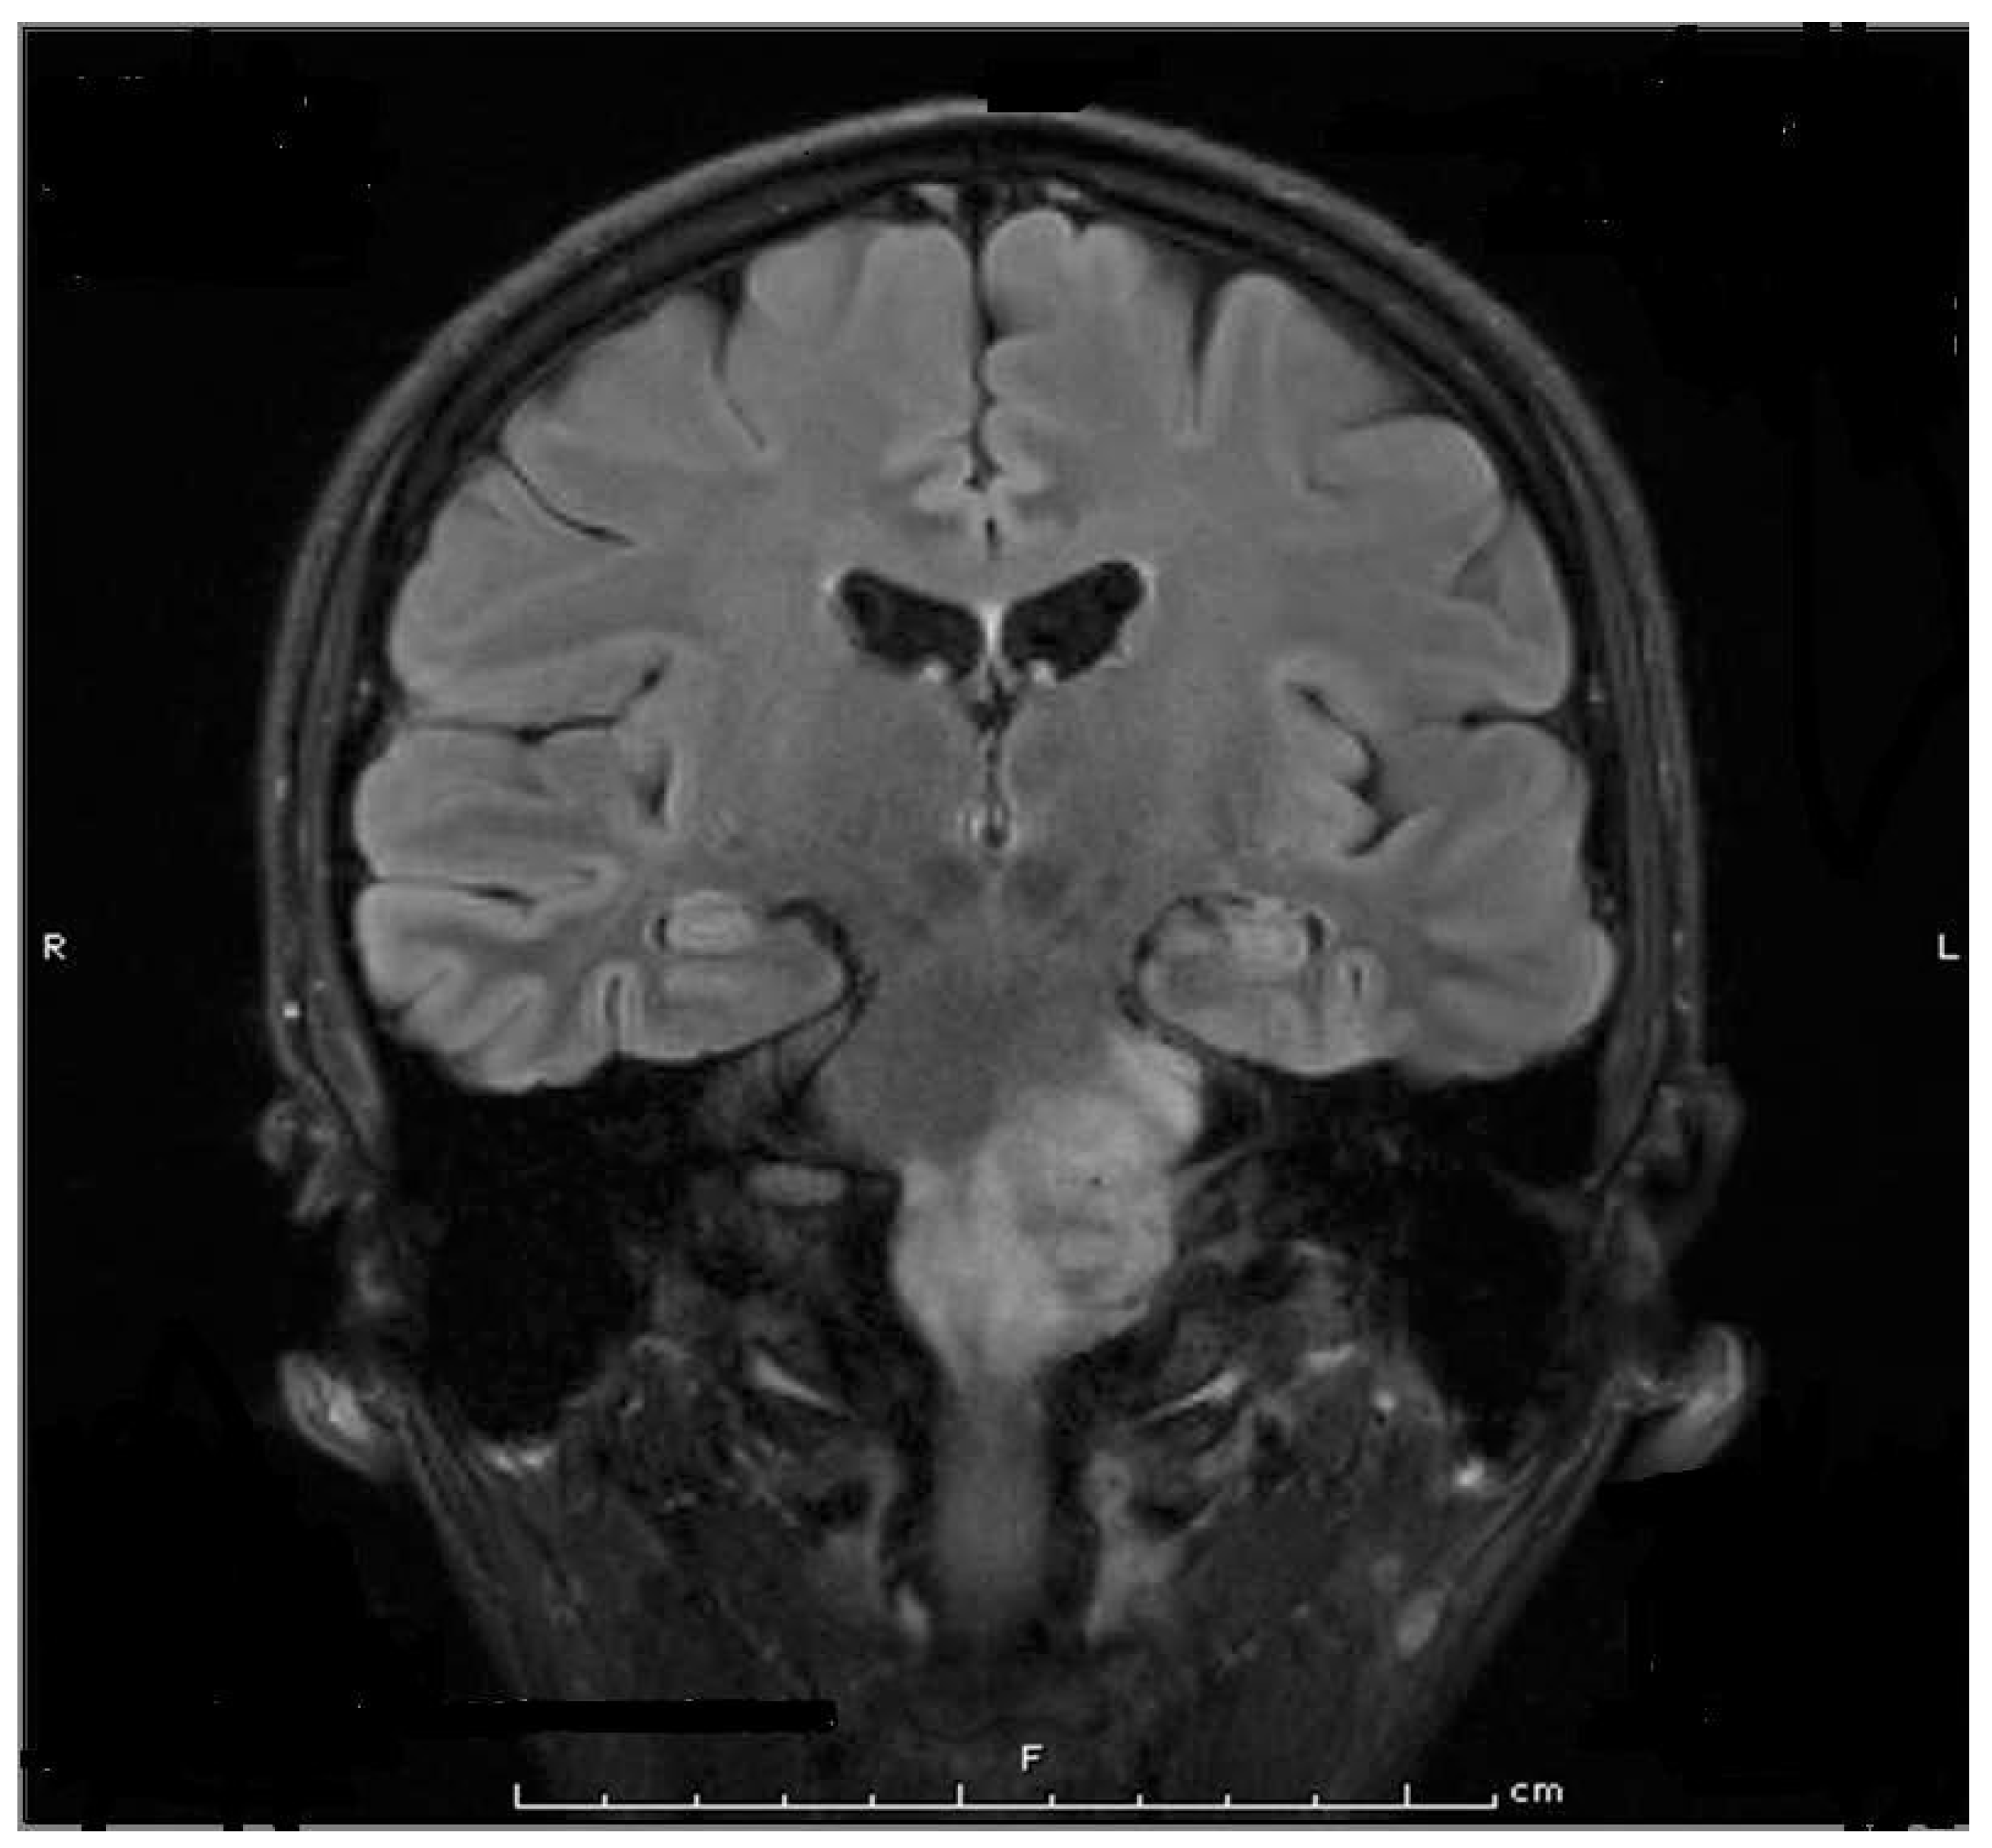

8. Parotidectomy and Parotid Radiation

9. First Bite Syndrome